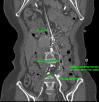

We present a case of a 61 years old lady operated 2 years back for severe superior mesenteric artery stenosis with a surgical vascular graft and presenting as acute severe abdominal pain and vomiting. Her CT angiography showed occlusion of the surgical vascular graft with graft migration into small bowel. Both the findings of graft occlusion and bowel perforation were optimally demonstrated on the CT angiography study. The alarm of bowel perforation in addition to graft infection was raised by the presence of air pockets within the graft and its communication with bowel lumen. Coexistent graft infection was evident on graft culture.